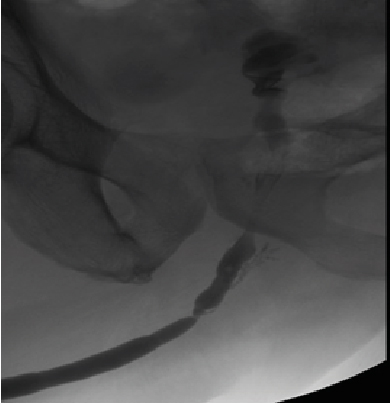

Retrograde urethrography is a very dynamic study, which must be taken into account when acquiring images, especially when sending still images, a common error is the leakage of contrast towards the skin (Figure 1) avoiding using a Foley catheter at the level of distal urethra to retain the contrast, however it can condition trauma [1]. Another common error is the ignorance of ideal projections for evaluation of the urethra (Figure 2), for example the Lauenstein projection, which is more useful for evaluating the hip. The imaging with a lack of contrast between the structures (Figure 3), which can be modified during and after the acquisition. It should be noted that on some occasions, in case of doubt, images will be taken from two different x-ray directions.

Figure 3: Lack of Contrast of the Structures, Either When Acquiring Them and Not Making Adjustments after the Process